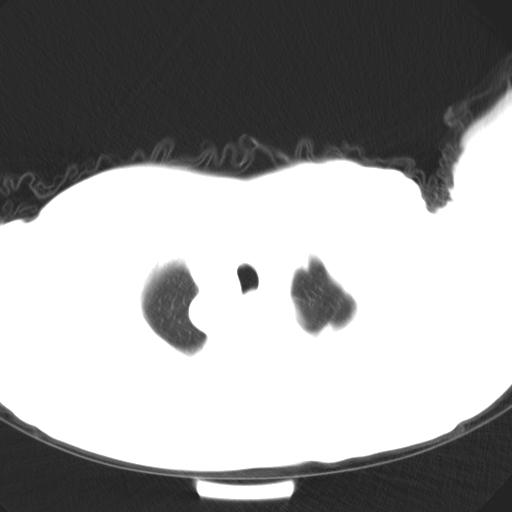

标题: CT25454:男,51岁,体检时发现右上纵隔高密度影。请会诊! [打印本页]

标题: CT25454:男,51岁,体检时发现右上纵隔高密度影。请会诊!

男,51岁,体检时发现右上纵隔高密度影。

右上纵隔脊柱旁圆形结节,密度均匀,边界清楚——考虑神经源性肿瘤!